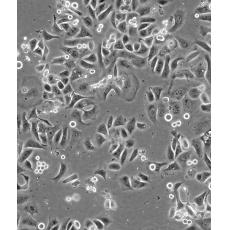

SK-BR-3 [SKBR-3;SKBR3]

產品名稱 SK-BR-3 [SKBR-3;SKBR3]

中文名稱 人乳腺腺癌細胞

組織來源 mammary gland/breast; derived from metastatic site: pleural effusion

細胞種屬 Homo sapiens, human

生長特性 adherent

形態特征 epithelial

細胞描述 he patient, a White, Caucasian female, age 43, blood type A+, had been treated with radiation, steroids, cytoxan and 5-fluorouracil.No virus particles.Ultrastructural features include microvilli and desmosomes, glycogen granules, large lysosomes, bundles of cytoplasmic fibrils.The SKBR- 3 cell line overexpresses the HER2/c-erb-2 gene product.